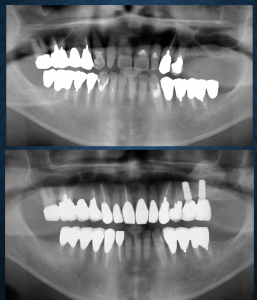

最初のケースは大学病院で骨が足りないからインプラントはできないと言われ(歯学部のない医科大学)、取り外し式の部分入れ歯を入れられたがほとんど使用していない方でした。このケースでは咬み合わせの平面が左右対称かどうかの診断、咬み合わせの高さが適切な範囲内かどうかの診断を行い、残存歯の数本に対して歯周外科処置、欠損に対してはサイナスリフトと呼ばれる副鼻腔内に骨を造る手術を行い、インプラントで修復し、天然歯と共にバランスがいいと考えられる形態で補綴(被せもの)しました。術前と比較した写真を見せると患者さんは大喜びでした。

2番目のケースは上は治療用入れ歯から本入れ歯(総義歯)、下の天然歯数本に歯周組織再生療法を行い、歯冠補綴を行いました。